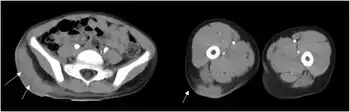

| CT images of lesion showing enhancing hypodense areas(Basidiobolomycosis caused by Basidiobolus meristosporus) | |

A review in 2015 showed that the most common finding on imaging of the abdomen was a mass in the bowel, the liver, or multiple sites and bowel wall thickening. Initially, many were considered to have either a cancer of the bowel or Crohns disease.[6][7]